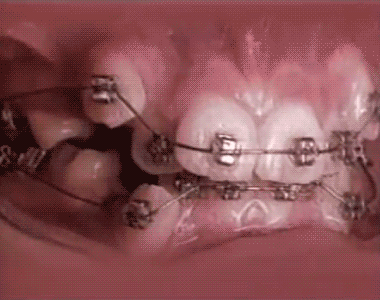

Esta es la vista acelerada del proceso de corrección dental con los brackets